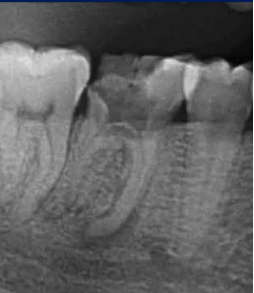

二次拍根尖片确认可看到根尖低密度炎症,临床检查与影像学检查相符,是根尖周炎。

曲面断层片怎么看口腔精读 | 一次性教你看懂曲面断层片!_https://www.jmylbn.com_新闻资讯_第21张

临床检查时发现14残根,牙龈红肿。曲面断层片上由于前磨牙转角问题,看不到残根,无法明确到底有没有残根,无法通过曲面断层片进行确诊或评估。

这时需要加拍根尖片,很明显能看到残根。这就说明,有曲面断层片也不能排除情况。

临床检查45叩诊(+),牙颌面见畸形中央尖。加拍根尖片可看到,右下5根方有低密度影,并且右下5的牙根较短小,和曲面断层片上显示的大小不同,所以右下5是舌向倾斜的牙齿。